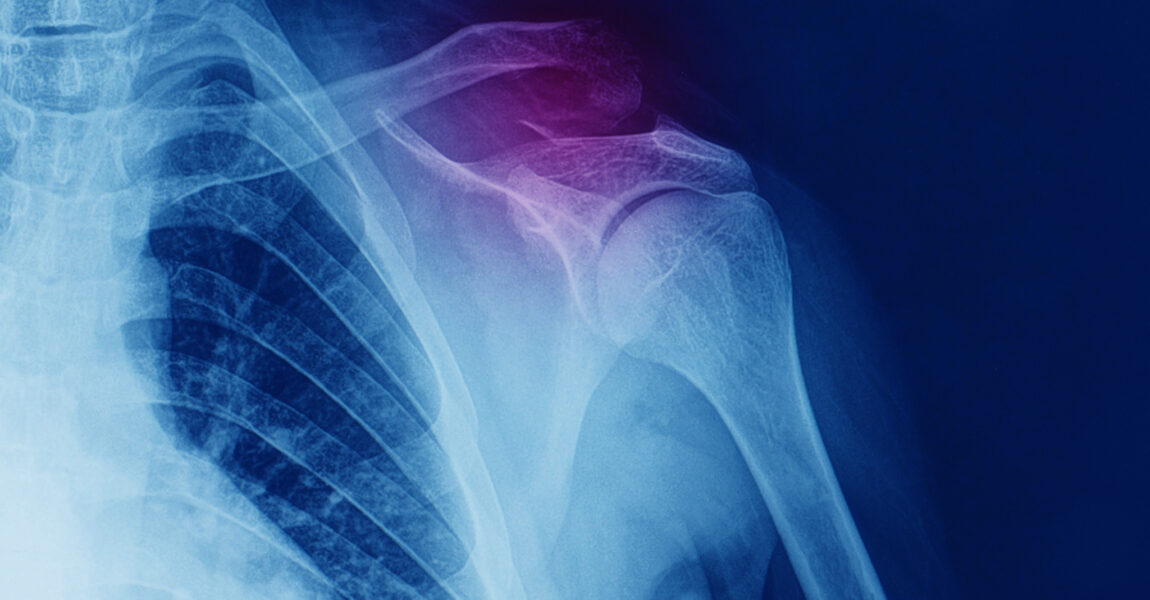

Fracture is a term that refers to a partial or complete break of a bone. If the shattered bone pokes through the skin and can be seen, or when a deep incision exposes the bone through the skin, it is called an open or compound fracture. If the bone is shattered but the skin remains intact, it is called a closed or simple fracture. Fractures are often the result of falls, injuries, accidents, or a direct hit or kick to the body.